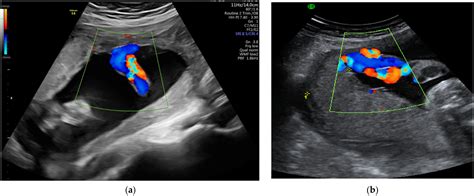

Diagnosis of a Short Umbilical Cord

Diagnosing a short umbilical cord typically involves ultrasound examinations. Ultrasound technology allows healthcare providers to visualize the umbilical cord and measure its length. Regular prenatal check-ups and ultrasounds can help detect this condition early in the pregnancy. Early detection is crucial for managing the risks associated with a short umbilical cord.

Research has also shown that the use of advanced ultrasound techniques can improve the accuracy of diagnosing a short umbilical cord. These techniques allow for more detailed imaging of the umbilical cord and placenta, providing valuable information for healthcare providers.